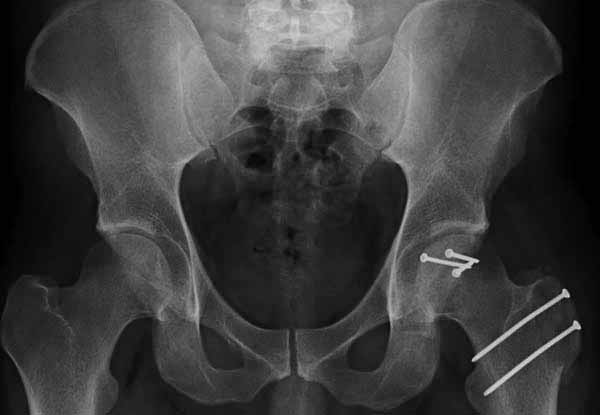

При сопутствующем переломе головки с ацетабулум, тогда артротомия из того доступа, который позволит фиксировать перелом впадины и фиксировать головку шурупами. На сегодня Headless Screw Synthes имеет преимущества перед другими, но при отстутствии их можно сделать обычными 3.5 мм., только головку надо утопить. При изолированном переломе доступ через trochanteric flip approach, который позволяет вывихнуть головку из ацетабулума и свободно работать без риска АВН. В вашем случае можно из переднего Smith Petersen доступа, потому что осколок спереди.

Представлены несколько вариантов фиксации: первый случай перелом головки с задним краем, операция из заднего доступа Кохер, а второй случай изолированный перелом головки - из трохантерного доступа.